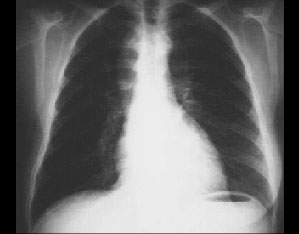

Your choice: Right-sided aortic arch

This overpenetrated chest X ray clearly demonstrates the right-sided aortic arch. While it may be found in patients who are otherwise normal, it is commonly associated with congenital cardiac abnormalities, including tetralogy of Fallot.